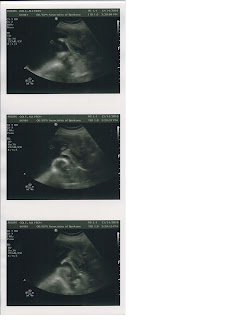

Ultrasound Pics - 19 weeks

Here is our baby girl's profile picture - I think she has very "Angelina Jolie-esque" lips

Here is her "girl" shot - boys don't look

And for those of you that know me from my gymnastics days...here she is taking after her mommy being very flexible with her little feet all the way up above her head